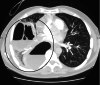

The Streptococcus anginosus group (SAG) consists of three bacteria (Streptococcus intermedius, Streptococcus constellatus, and Streptococcus anginosus) that are known commensals of the upper respiratory, digestive, and reproductive tracts. While a rare occurrence, these bacteria have the capability of causing devastating pyogenic infections and ensuing abscess formations. It is often difficult to distinguish this group as a contaminant or the offending organism (as it is often cultured in respiratory specimens); therefore, it is important to understand the risk factors, clinical presentation, and diagnostic findings that can provide a more accurate picture to identify the organism. Published literature pertaining to the SAG group has rarely documented any invasive surgical intervention that was undertaken for treatment. We describe a case of a 59-year-old male who presented for persistent chest pain and profuse productive cough weeks after he was diagnosed with a left lower extremity deep vein thrombosis and right-sided pulmonary embolism. The patient was found to have a rapidly evolving Streptococcus constellatus right middle lobe lung abscess complicated by a right hemithorax empyema. Management included an exploration of the right chest, decortication, parietal pleurectomy, and partial excision of the right middle lobe. Subsequently, the patient completed four weeks of antibiotics with ertapenem.